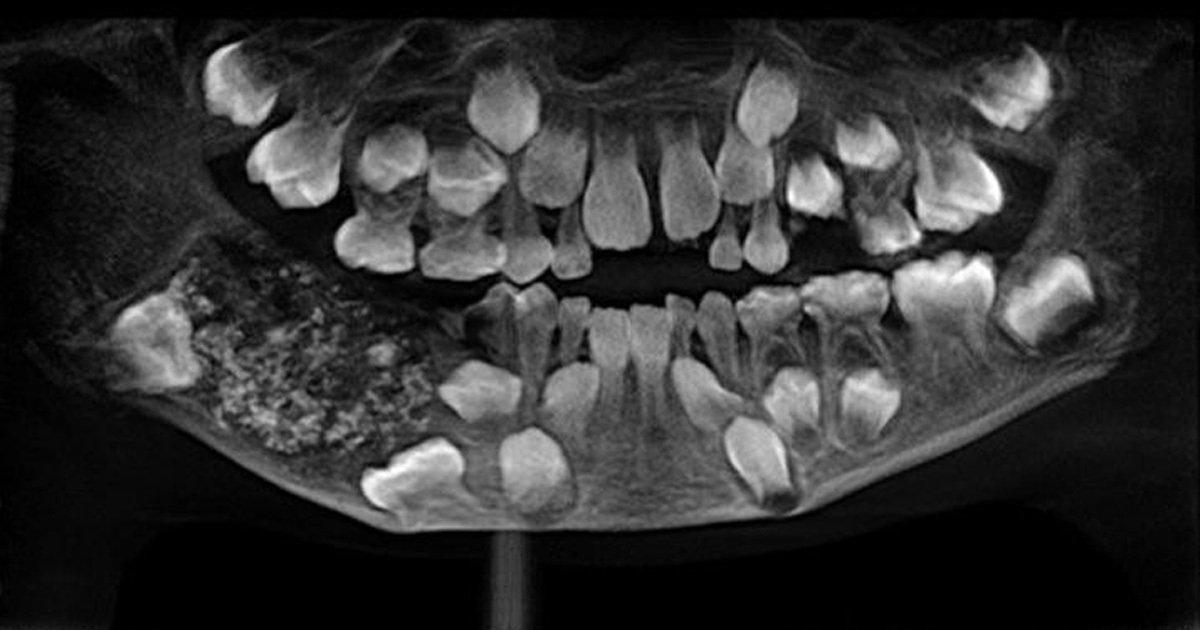

▼印度一位7歲的男孩日前到清奈(Chennai)的醫院看診,並向醫生抱怨自己下顎右方臼齒附近很腫,醫生Prathiba Ramani為他進行X光檢查後,發現他下顎部分有一塊肉囊腫。

▼醫生動刀將囊腫從他嘴中取出,再花了4-5小時清空裡頭的東西,發現內部足足有526顆牙齒。醫生解釋:「我們沒有從側面打碎骨頭取出,這樣他就不用再進行額外的重建手術。囊腫就像一個膨脹的氣球,你可以想像裡頭充滿了許多碎片。」

▼醫生驚訝表示,這526顆牙齒都長得非常「完整」,它們的大小從0.1毫米到15毫米都有。但即使是最小的牙齒,也具備了牙冠、牙根和琺瑯質,可明確知道這是一個牙齒。

▼醫生解釋,這位小男孩應該是罹患了罕有的「組合型複合性牙瘤」,這類狀況會長出正常的牙齒,但排列發生異常,所以才會冒出層層小牙齒。目前原因還無法確定,有可能是遺傳因素,或是遭到輻射。